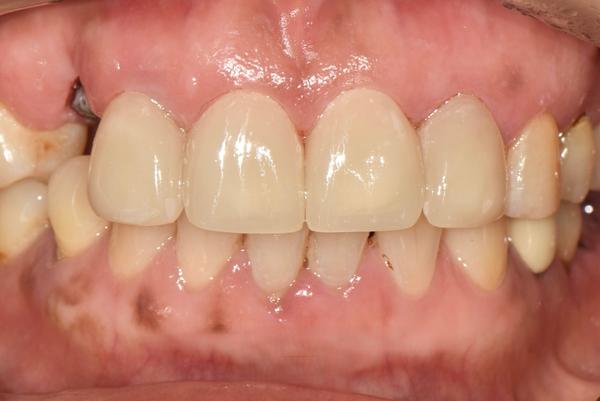

ハル歯科医院は、最先端のインプラント歯科治療に特化したクリニックです。代表のジョー・ハング院長は日本の神奈川歯科大学を卒業し、両国での歯科医師免許を保持。さらに、韓国で専門医資格を取得し、口腔外科など高度な手術経験も豊富です。すべての治療を院長自らが行う専任診療制を採用しており、流暢な日本語で対応可能。「デジタルインプラント」や「無削除ラミネート」などの最新のデジタル歯科治療を、日本の約半額で受けられます。仁川・金浦空港から乗り換えなしで行ける孔徳(コンドッ)駅すぐとアクセスも良好で、旅行者にも便利な立地となっています。